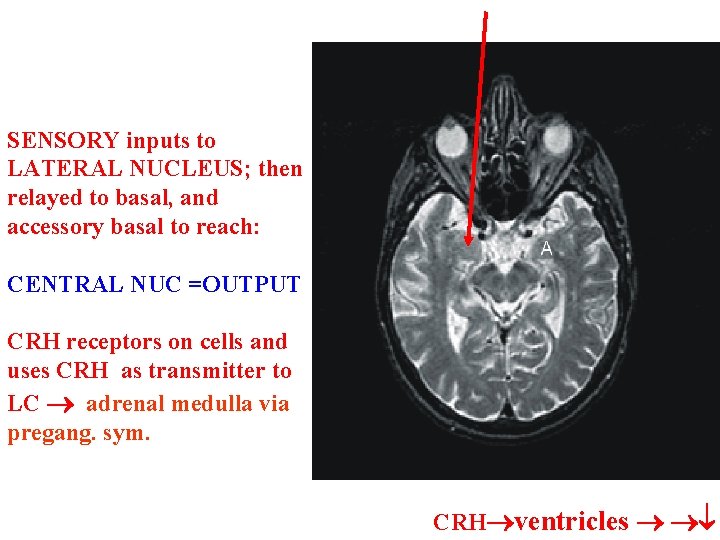

SENSORY inputs to LATERAL NUCLEUS; then relayed to basal, and accessory basal to reach: CENTRAL NUC =OUTPUT CRH receptors on cells and uses CRH as transmitter to LC adrenal medulla via pregang. sym. CRH ventricles

CRH into severe ventricles=turn on fear response and hypervigilance; CRH antagonists central nuc=reduction in the occurrence of above reactions • Target CRHCRH Amyg. conn